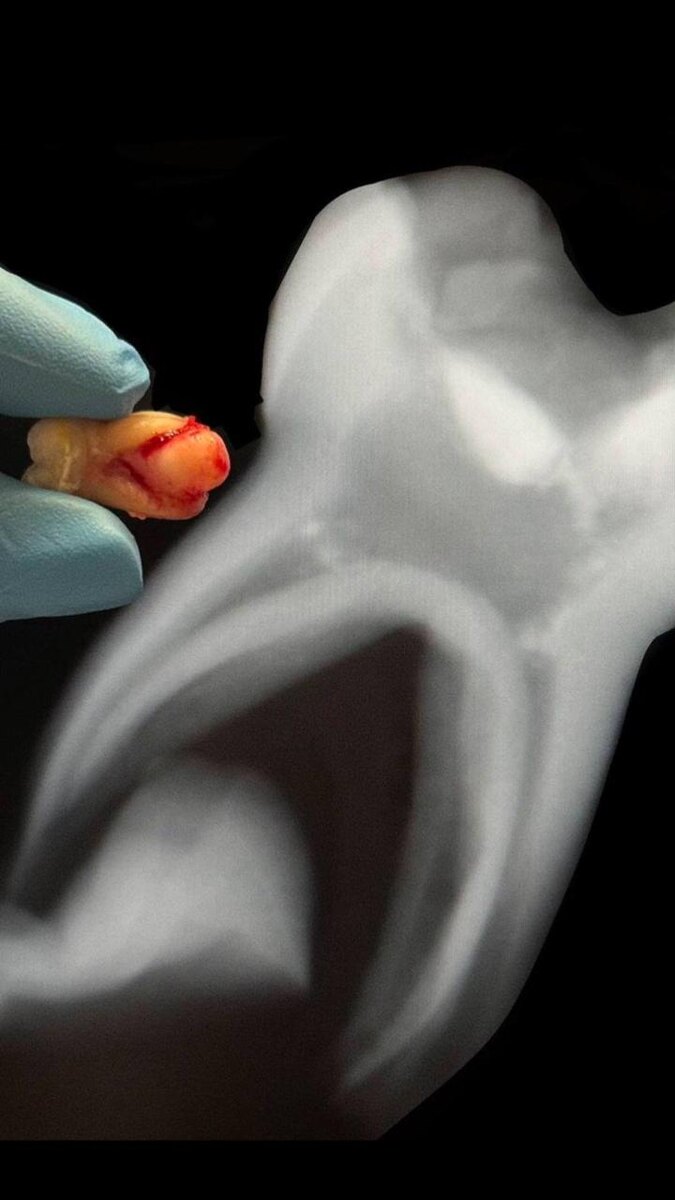

Воспалительный процесс в молочном зубе зашёл так глубоко, что затронул кость и даже дошёл до постоянного зуба. На фото, которое вы видите, рядом молочный и постоянный зуб. И, к сожалению, зачаток постоянного зуба уже спасти не удалось. Именно молочные зубы – это защита и основа для постоянных зубов, в этой истории мы видим, как важно их беречь. Поэтому, когда мы, детские стоматологи, говорим, что молочные зубы нужно лечить – это не преувеличение. Это реальная необходимость, чтобы воспаление не пошло дальше и не повредило постоянные зубы 📍 В следующем посте я расскажу подробнее, о последствиях такой ситуации 〰️

Воспалительный процесс в молочном зубе

зашёл так глубоко, что затронул кость и даже дошёл до постоянного зуба. На фото, которое вы видите, рядом молочный и постоянный зуб. И, к сожалению, зачаток постоянного зуба уже спасти не удалось.

Именно молочные зубы – это защита и основа для постоянных зубов, в этой истории мы видим, как важно их беречь.

Поэтому, когда мы, детские стоматологи, говорим, что молочные зубы нужно лечить – это не преувеличение. Это реальная необходимость, чтобы воспаление не пошло дальше и не повредило постоянные зубы 📍